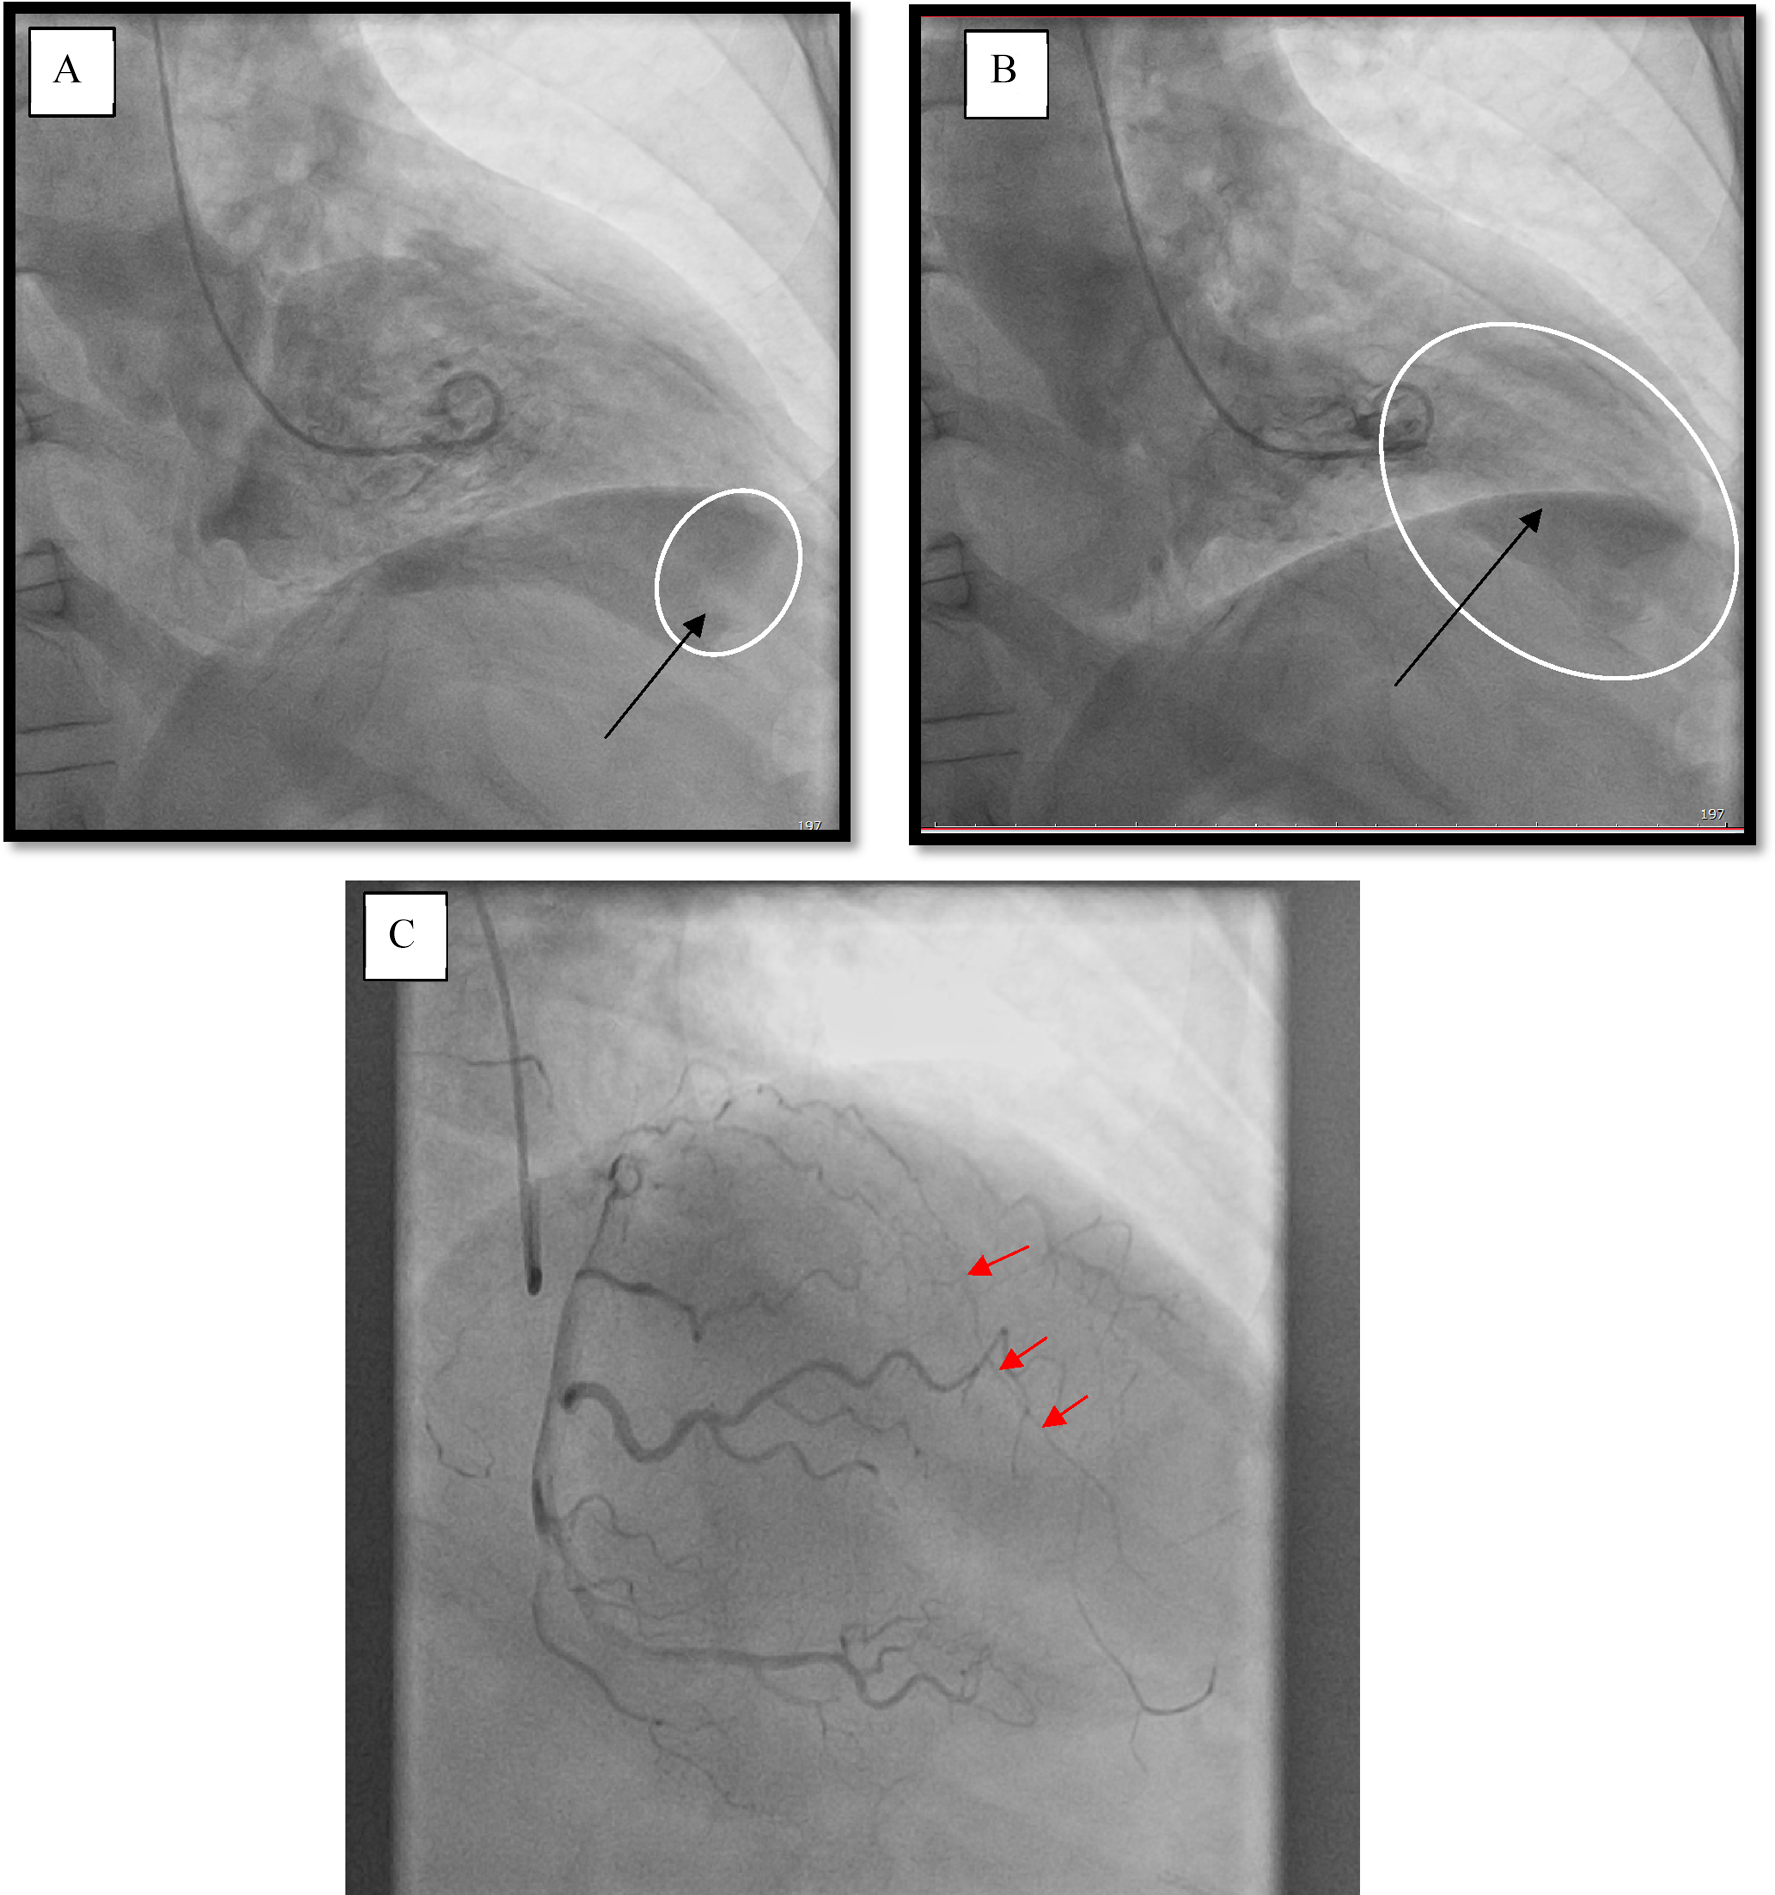

A male patient (66 years of age, weighing 80 kg) was sent to our Center with signs of the functional class III heart failure and diagnosed with thrombosed PLVA. Upon admission to the department, the diagnosis was confirmed by electrocardiography, echocardiography (EchoCG), and ventriculography. The ECG is specific, it is shown in Figure 1. EchoCG data revealed an enlarged LV with the left ventricular end-diastolic volume (LV EDV) of 177 ml, end-sistolic volume (LV ESV)—116.8 ml, EDV index—88.5 ml/m2, ESV index—58.4 ml/m2, a change in its shape (left ventricular sphericity index of 0.65 in diastole and apical conicity index of 0.93 in systole), areas of hypo- and akinesia with the formation of a thrombosed aneurysm of anterolateral segment with transition to the apex (aneurysm volume of 56 ml, thrombus size of 17 × 29 mm), and also a reduction in global contractility of the LV myocardium characterized by the left ventricular ejection fraction (LVEF) of 34%. Left ventriculography in two projections confirmed the fact of pronounced negative remodeling of the LV in the form of an aneurysm with thrombus formation (Figures 2A,B).

Figure 2

Left ventriculography. (A) Diastole, the arrow points at a thrombus at the left ventricle apex. (B) Systole, the arrow indicates the area of the aneurysm. (C) Coronary catheterization. The arrows point at the occlusion of the left anterior descending branch of the left coronary artery (LAD LCA).

According to the results of coronary catheterization, occlusion of the left anterior descending branch of the left coronary artery (LAD LCA) was noted without proper filling of the lumen along intersystem and intrasystem collaterals (Figure 2C).